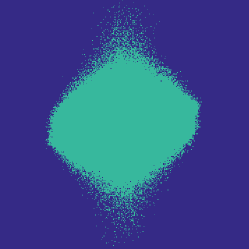

![]() |

| 6.25% sampling | 12.5% sampling | 25% sampling |

Figure 1 illustrates the best performing randomized indices and our learned set of indices in the plane of the -space. Both the variable density approach [14] and our learning-based approach concentrates its sampling budget on the low frequencies, however the latter is endowed with the capability to adapt its frequency selection to the frequency content of the training signals instead of assuming a circularly symmetric selection.